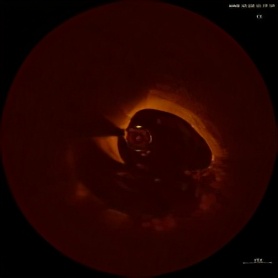

黄某,男,39岁,“因反复胸闷,心悸10天”入院,上周冠脉造影提示左回旋支近段99%局限性狭窄,右冠近段30%狭窄(可疑不稳定斑块),上周对回旋支病变植入一枚支架,但右冠病变是否需要处理仅凭造影不能明确。今日行OCT检查,提示右冠近段病变实际上为冠脉夹层伴有菲薄的脂质纤维帽,在OCT指导下,顺利为患者病变处植入一枚支架,术后OCT结果显示支架贴壁良好,夹层消失,术后患者胸闷明显改善。

薄纤维帽

冠脉夹层

术前

术后